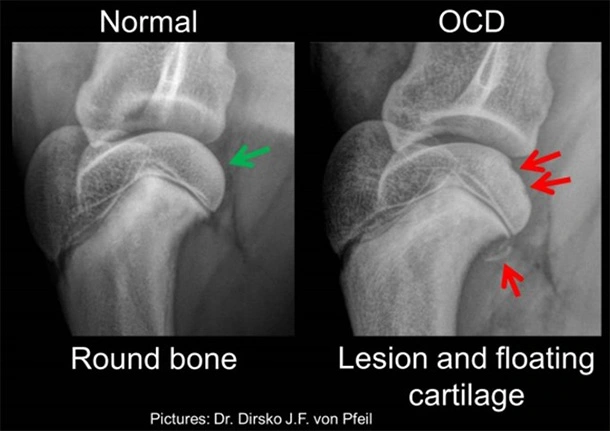

Osteochondrosis Dissecans

Osteochondrosis Dissecans (Osteochondrose, Knorpelschaden im Gelenk)

Oft diagnostiziert mittels computertomographischer Bildgebung, und behandelt via Arthroskopie.

Diese Problematik ist typischerweise bei jungen, grosswüchsigen Hunden ein Grund für Lahmheit.

Beispiel einer normalen (links) und einer von OCD betroffenen Schulter (rechts). Beachten Sie die runde Form des Knochens in der normalen Schulter (grüner Pfeil) im Gegensatz zum Defekt und die "Gelenkmaus" in der erkrankten Schulter (rote Pfeile).

Arthroskopische Ansicht einer OCD-Läsion der Schulter. Der erkrankte Knorpellappen wird vom darunter liegenden Knochenbett abgehoben. Anschließend wird er aus dem Gelenk entfernt, um eine schmerzfreie Bewegung zu ermöglichen.